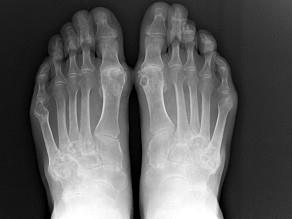

问题 男,72岁,手足小关节红肿热痛,白细胞升高,血沉快,血尿酸升高,结合图像,最可能诊断是?(?)

选项 A.类风湿关节炎 B.退行性骨关节病 C.痛风性关节炎 D.假痛风 E.滑膜炎

答案 C